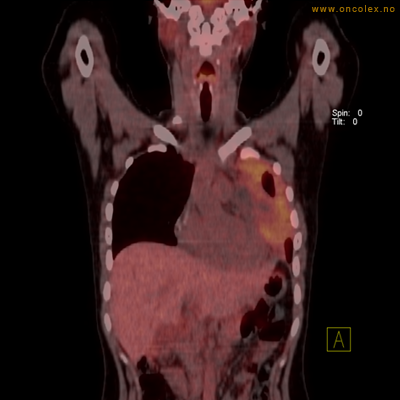

PET/CT (PET: Positron Emisjons Tomografi/ CT: Computer Tomografi) er en avansert nukleærmedisinsk bildetakingsmetode. Metoden er et godt dokumentert, veletablert og svært nyttig verktøy i bildediagnostikk ved kreft. Et PET-kamera gir tredimensjonale bilder av hele kroppen. Integrert CT gjør at informasjonen fra PET blir lokalisert anatomisk nøyaktig.

Kort beskrivelse av undersøkelsen

Gjennom en nål (plastkanyle) i en blodåre i armen vil du få et radioaktivt stoff. Det mest vanlige er radioaktivt druesukker (18F-FDG). Stråling fra det radioaktive stoffet registreres i PET-skanneren og viser hvordan dette stoffet fordeler seg i kroppen. Det normale opptaket av det radioaktive stoffet vil være endret ved sykdomsprosesser. Celler med høyt stoffskite, som for eksempel kreftceller, har økt opptak av sukker. Ved undersøkelsen kan man dermed ofte se større opptak av det radioaktive sporstoffet i kreftsvulster.  Siden CT tas samtidig, kan PET og CT bildene legges sammen og vise nøyaktig hvor i kroppen det økte opptaket er.

Eksempler på funn

Vev som tar opp mer radioaktivt stoff, synes som hvite områder som lyser opp mer i forhold til annet vev som tar opp mindre sukker.